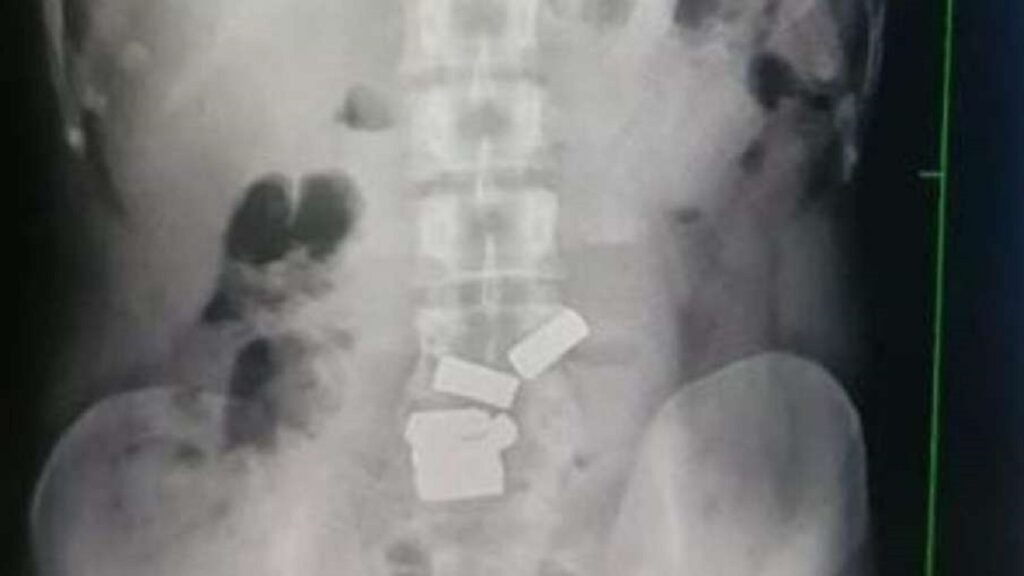

After the disclosure of the accused, the officials of the Customs Department got his X-ray done at JJ Hospital. This was confirmed in X-ray. Disclosing the matter, custom officials said that the value of the recovered gold is about Rs 1.5 crore. The officials also informed that the man was taken to JJ Hospital. Where a team led by Dr. Ajay Bhandarwar, head of the surgery department, took out all the 7 gold pieces from the man’s stomach in a natural way.